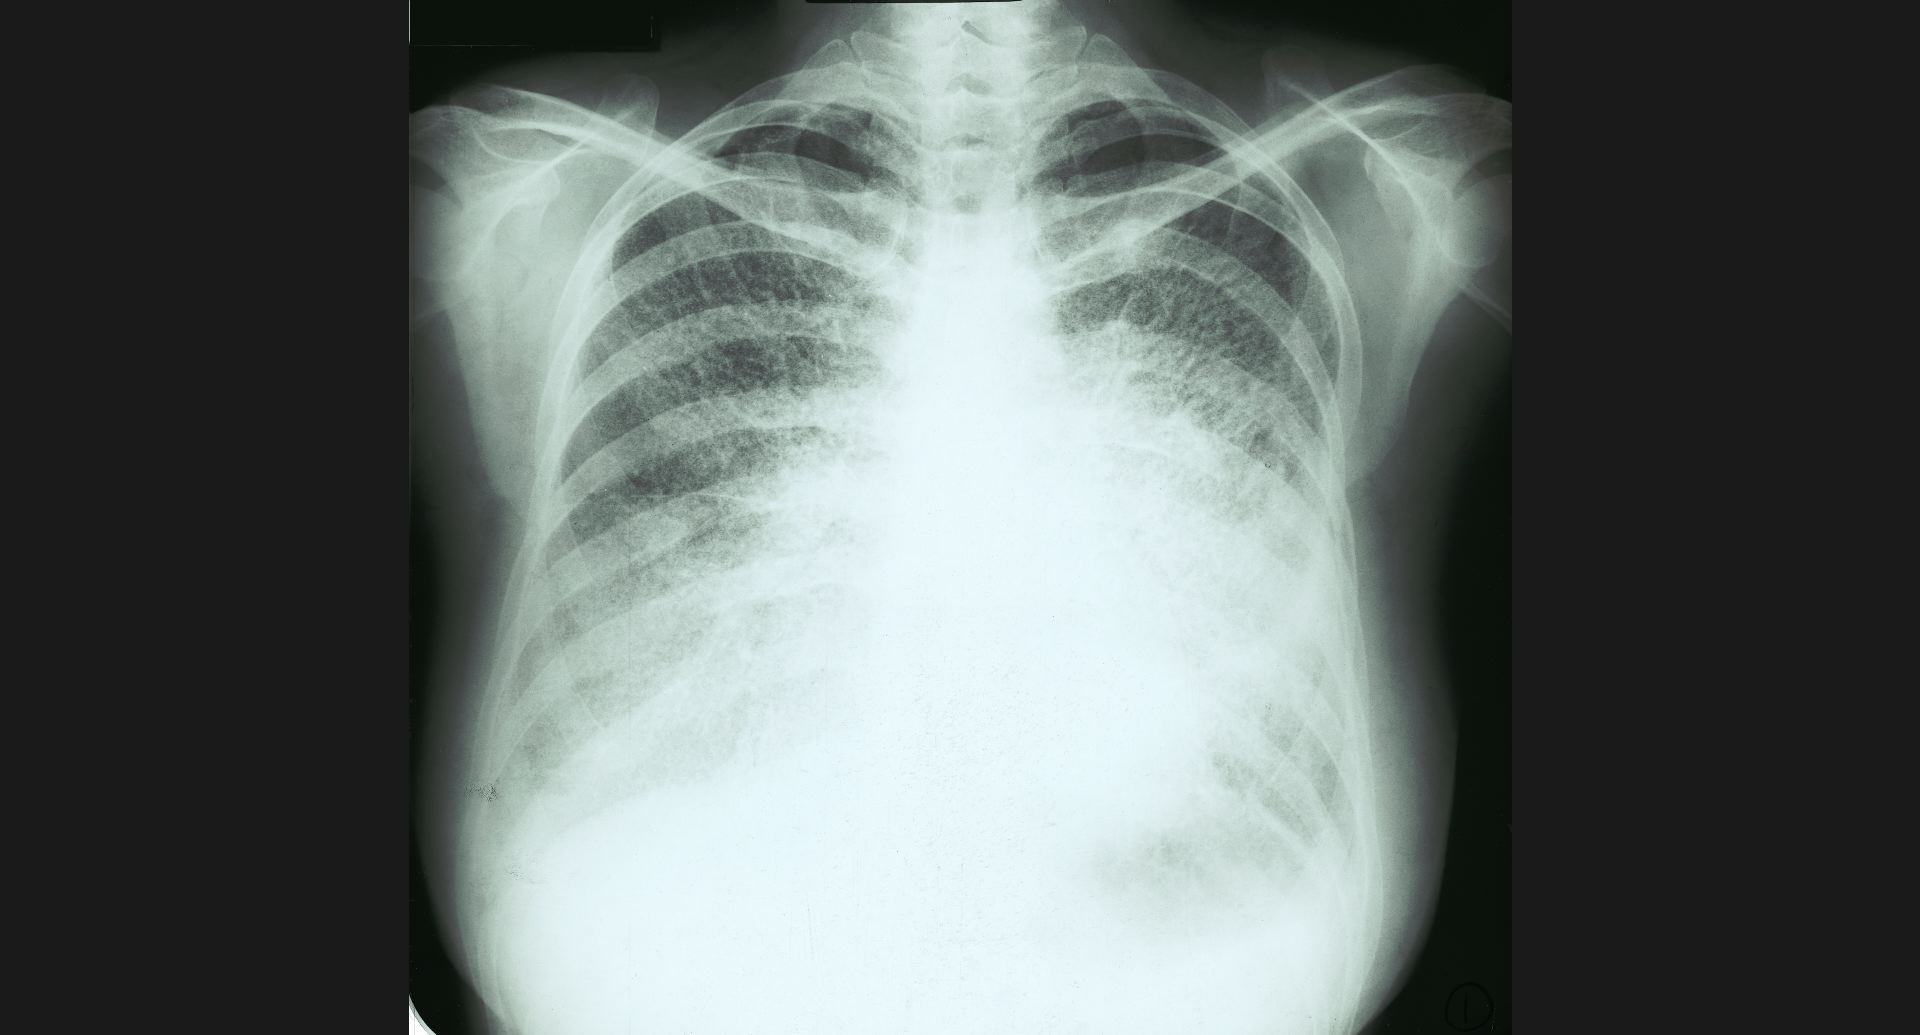

fig.1(117KB)

:Alveolar microlithiasis細かい肺病変、air bronchogram。